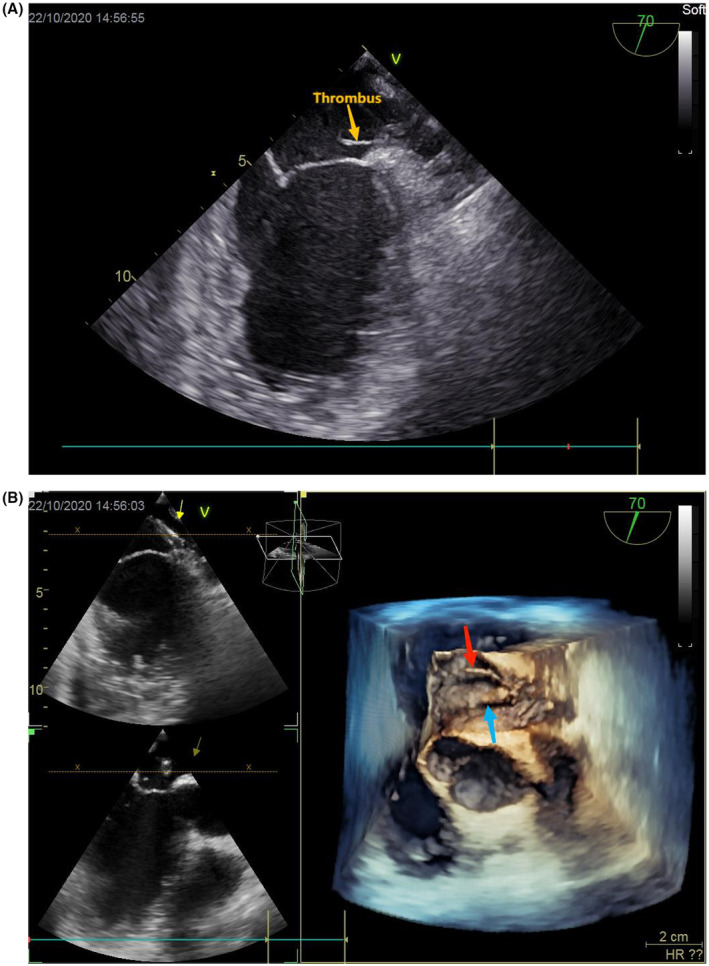

An 6F sheath was placed in the right femoral vein; intravenous heparin 3000 U was administered. After transesophageal echocardiography (TEE)‐guided trans‐septal puncture, heparin 4500 U was given. Then, a 12F delivery sheath and pigtail catheter were positioned in the LAA. Activated clotting time (ACT) measured 254 s. An angiogram and TEE were performed to assess the appendage morphology. TEE revealed a cactus shaped LAA free of thrombus. LAA emptying velocity was 40 cm/s. Mild spontaneous echocardiographic contrast was in the LAA. The patient then underwent successfully implantation of a 22‐mm LACbes device with no para‐device leak. After the occlusion device release, TEE showed a 20 mm length floating thrombus attached to the delivery sheath tip (Figure 1A,B). ACT was measured 112 s, and heparin 3000 U was added immediately. We tried to suck the thrombus through long sheath but failed. ACT measured 124 s after 5 min. Heparin was added in divided doses without any effect on the thrombus resolution. Cerebral embolic protection devices (ev3 SpiderFX) were implanted in the bilateral internal carotid arteries and urokinase 500,000 U was administered to achieve ACT >250 s until TEE showed thrombus dissolved. After thrombolytic therapy, cerebral and renal artery angiogram were conducted and showed no embolism sign. Thrombus debris was detected in the filter after removal (Figure 2). Rivaroxaban and aspirin were initiated, and the patient was closely monitored post‐operation. The neurological function was not impaired, and cerebral CT showed old infarcts 1 day after procedure.

FIGURE 1.

(A, B) 2D and 3D TEE showed a floating thrombus attached to the delivery sheath; 3D TEE view: yellow arrow indicate sheath and red arrow indicate thrombus.